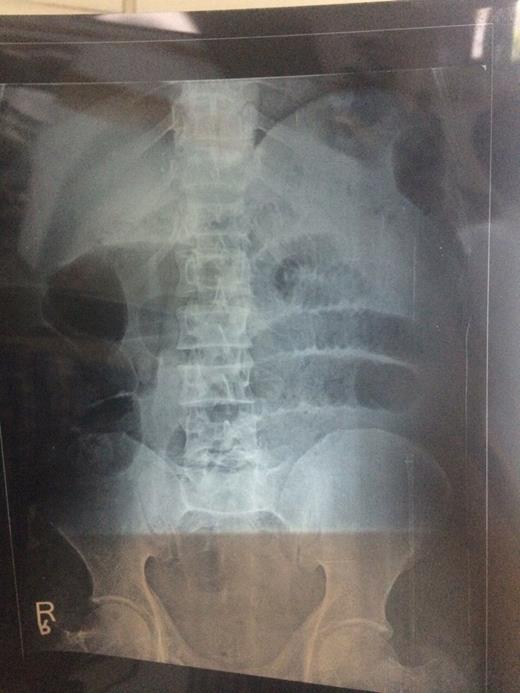

A 51-year-old male was brought in our casuality in shock with history of abdomen pain and non-passage of flatus and stools for 24 h. His blood pressure was 78/56 mmHg and pulse rate was 112 min−1. Abdomen was distended and tender. He was resuscitated, and X-ray of abdomen revealed multiple dilated gut loops as depicted in Fig. 1. Per rectal examination revealed soft faecal matter. Ultrasonography showed multiple dilated gut loops with minimal intergut fluid. CT was not available. Urgent exploratory laparotomy was done. Ileum was wrapped around sigmoid colon making two complete turns with gangrene of sigmoid colon and ileum as depicted in Fig. 2. Clamps applied on large gut and sigmoid colon removed followed by ileum, and end jejunostomy was done in view of haemodynamic unstability of the patient along with descending sigmoid colon anastomosis. The patient expired after 2 weeks despite exhaustive efforts due to complications of short bowl syndrome.

Intraoperative picture showing ileal knotting around sigmoid colon resulting in gangrene of both.